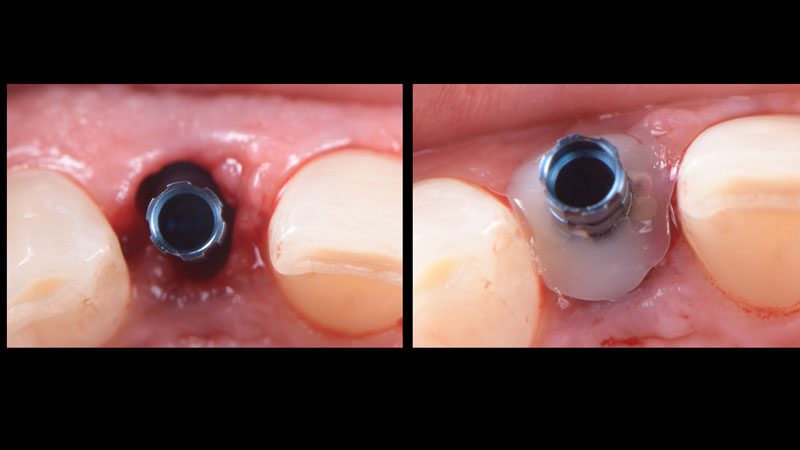

Hình 3. Sau khi đi mũi khoan đầu tiên và đặt pin định hướng (guide pin) để xác định lại hướng và vị trí Implant.

Hình 4. Đặt Implant Straumann BLT 2.9 x 14 mm.

Hình 5. Thực hiện một trụ Healing cá nhân bằng nhựa composite để duy trì cấu trúc mô mềm xung quanh.

Hình 6. Hình ảnh Healing cá nhân sau khi thực hiện.